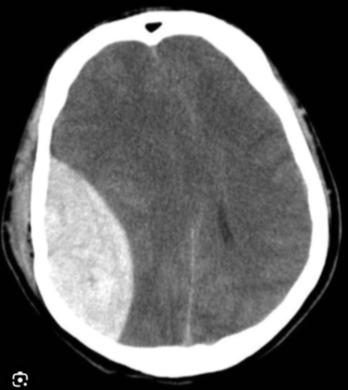

How does an extradural haematoma present on a CT head?

- Biconvex (lens-shaped) hyperdense collection

- Does not cross suture lines

- Causes mass effect with midline shift

- Compresses the adjacent lateral ventricle

- Often associated with a temporal bone fracture

- Acute blood appears bright white